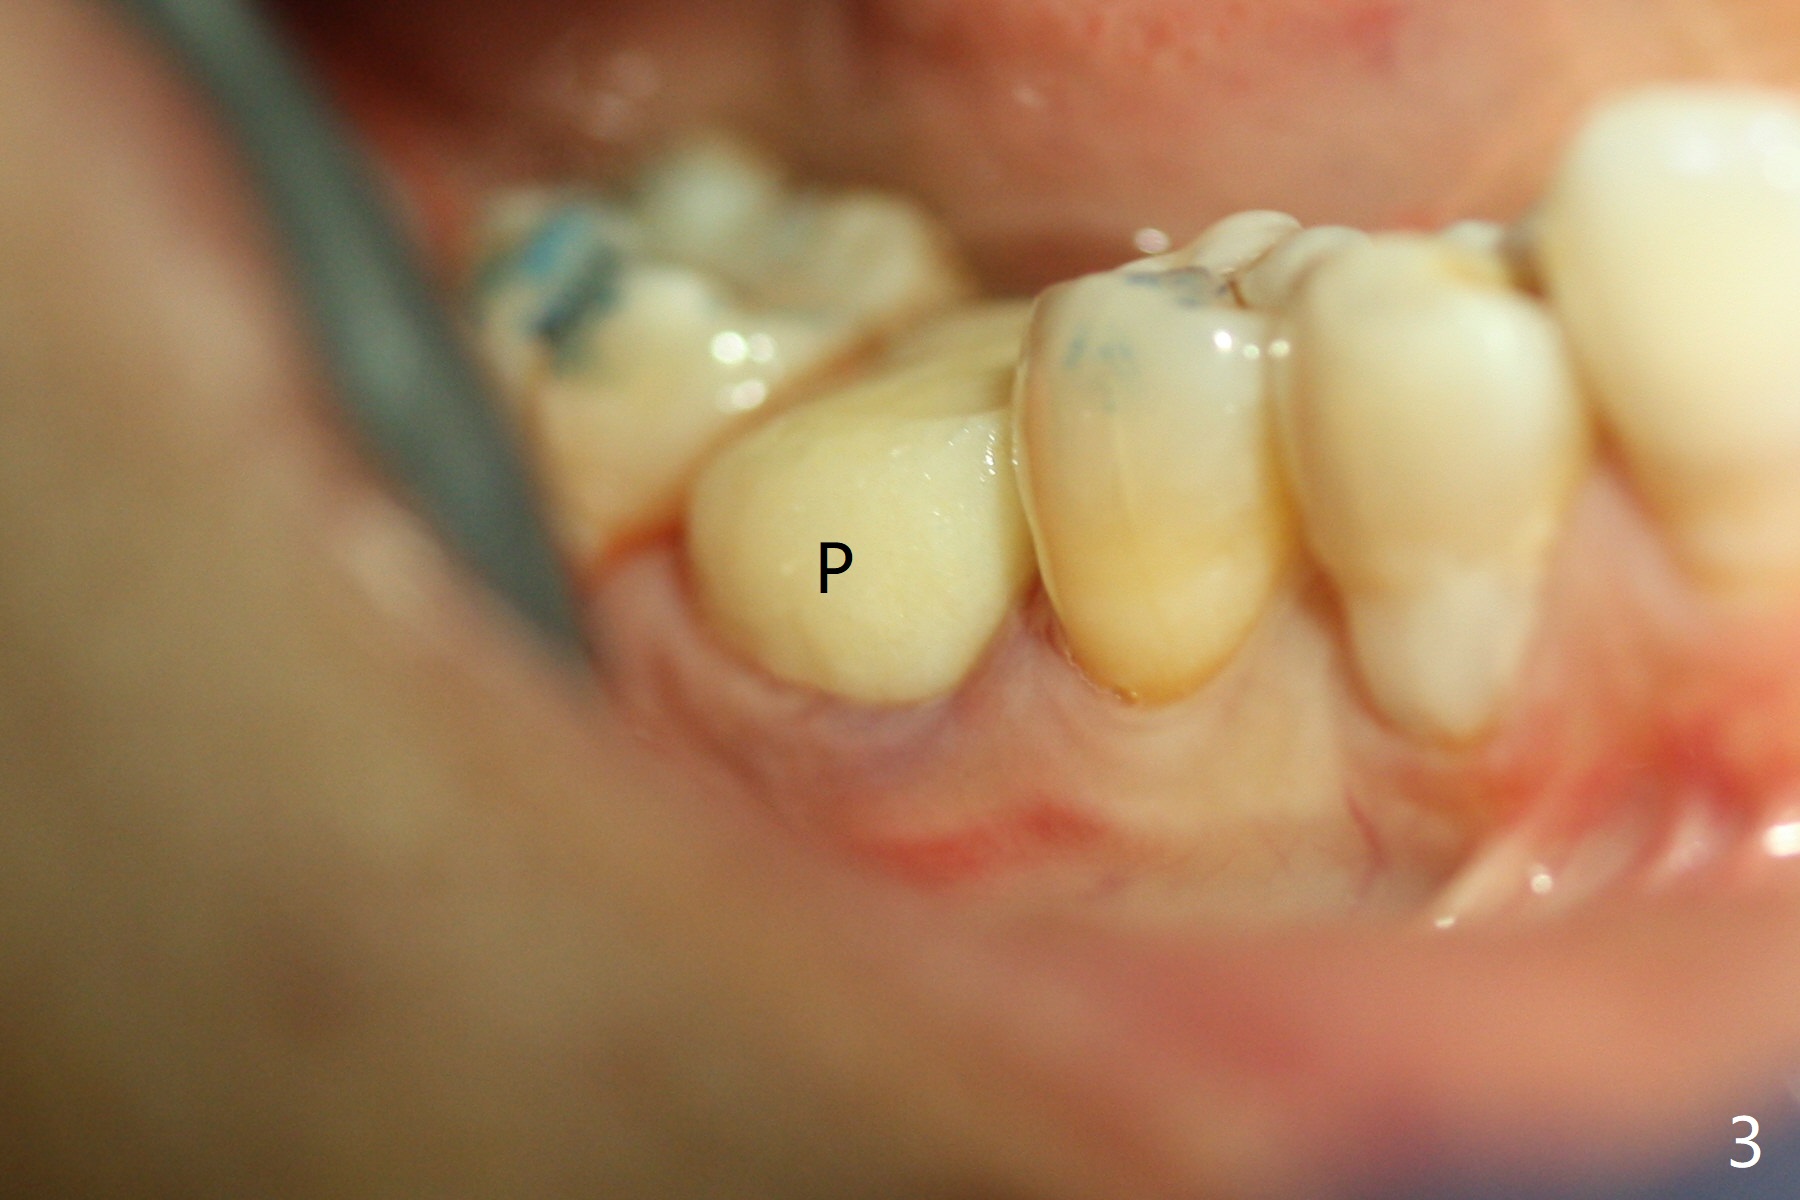

After extraction of #30 (Fig.1 (S: septum)), a 5x11.5 mm implant is placed with guide mainly in the mesial socket (mesial to the septum (S) with >35 Ncm; after immediate placement of a 6.5x4(3) mm abutment, allograft is placed (Fig.2 *). An immediate provisional is fabricated to hold the bone graft in place (Fig.3 P). To prevent micro-movement, the provisional has clearance from the opposing dentition (Fig.4 *, nonfunctional). There is not too much loss of bone graft 4 months postop (Fig.5). In fact the mesial and distal sockets heal. The implant plateau is covered with the bone 8 months post cementation (Fig.6 arrowheads ( *: addition of porcelain for the distal gingival embrasure)).